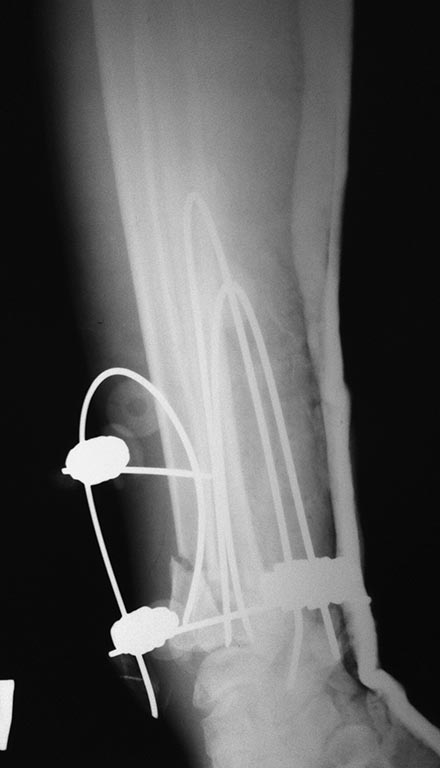

[Ortho] Остеосинтез н/3 предплечья

Р-граммы

Имя     : image (1).jpg